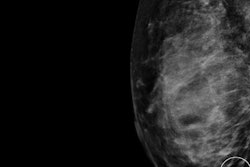

A Swedish group recently made the case for computer-aided detection software in breast cancer screening, highlighting the wide range of sensitivity of radiologists for finding cancer on mammograms. AI was also shown to improve tracking of liver lesion changes on MRI, and it can bolster radiologist performance in identifying hip fractures on radiographs.